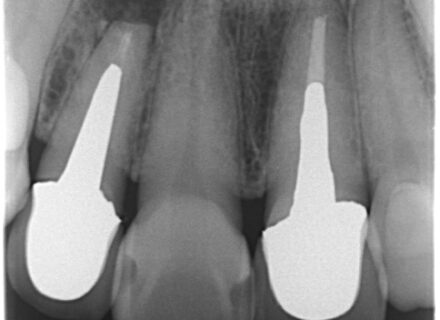

8年経過したインプラント症例:前歯の違和感を訴える40代女性患者 はじめに インプラント治療後の長期経過観察は、治療の成功を評価する上で非常に重要です。今回、8年前にインプラント治療を行った40代…